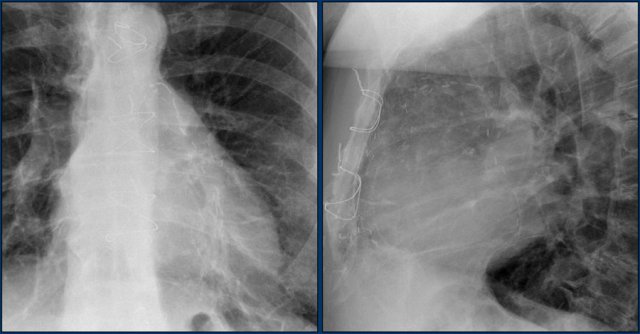

Images of a patient with an ASD and an Amplatz closure device.